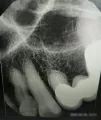

Зуб двойка подготовлен для вкладки под мост. Есть нюансы. Возможно ли проделать запланированную процедуру?

Комментарий №173385

• По данному рентгеновскому снимку зуб подлежит удалению, так как есть расширение периодонтальной щели, воспалительный процесс за верхушкой корня зуба, некачественно запломбированный корневой канал, мало здоровых твёрдых тканей зуба. Восстановление вкладкой и коронкой недолговечно в данном случае.